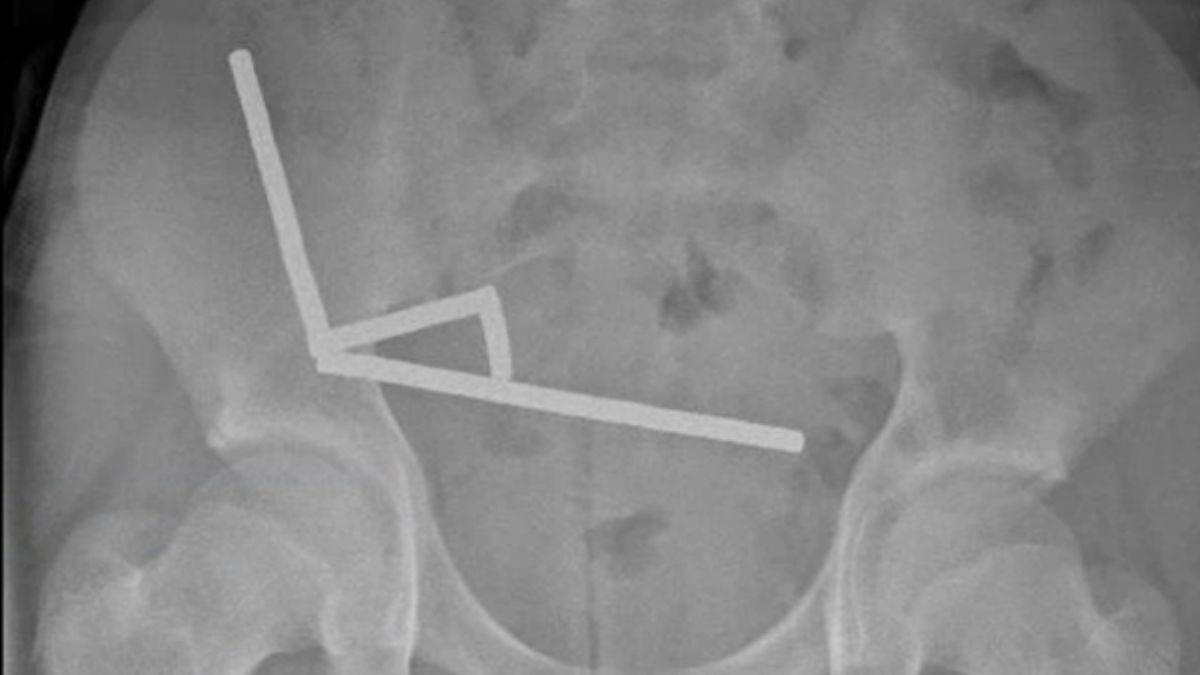

Folosind o radiografie, medicii au observat patru lanțuri lineare în părți separate ale intestinului băiatului.

În timpul intervenției chirurgicale, lanțurile au fost găsite în secțiuni separate ale intestinului subțire și cecum. Prin comprimare, acestea cauzau moartea mai multor porțiuni de țesut din lipsa de sânge, în ceea ce este cunoscut sub numele de necroză de presiune.